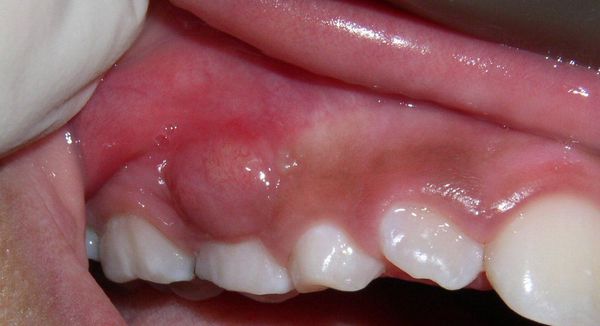

Ostre ropne zapalenie okostnej (stan zapalny błony pokrywającej kość z obecnością ropy) zazwyczaj nie powoduje ograniczenia otwierania ust. Podczas badania palpacyjnego węzłów chłonnych w okolicy zmiany często stwierdza się objawy ostrego zapalenia węzłów chłonnych (powiększenie i bolesność węzłów). Podczas badania jamy ustnej widoczny jest ząb przyczynowy (czyli ten, który wywołał stan zapalny), reagujący ostrym bólem na opukiwanie (perkusję) – z powodu zapalenia w okolicy wierzchołka jego korzenia. W przedsionku jamy ustnej stwierdza się naciek zapalny (zagęszczenie tkanek), bolesny przy dotyku; błona śluzowa nad nim jest obrzęknięta i zaczerwieniona (przekrwiona). Zgodnie z obserwacjami zapalenie okostnej częściej występuje od strony policzka lub wargi, a rzadziej – od strony podniebienia lub języka.